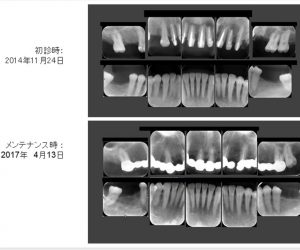

他院で抜歯と言われた歯を保存した症例

投稿日:2019年3月17日

この方は2014年11月に初診でいらした方です。 主訴は 「他院で多数抜歯して入れ歯にすると言われた。なるべく抜きたくないし入れ歯なんて絶対嫌!」 知り合いからの御紹介でいらっしゃいました。 初診時です 歯 […]